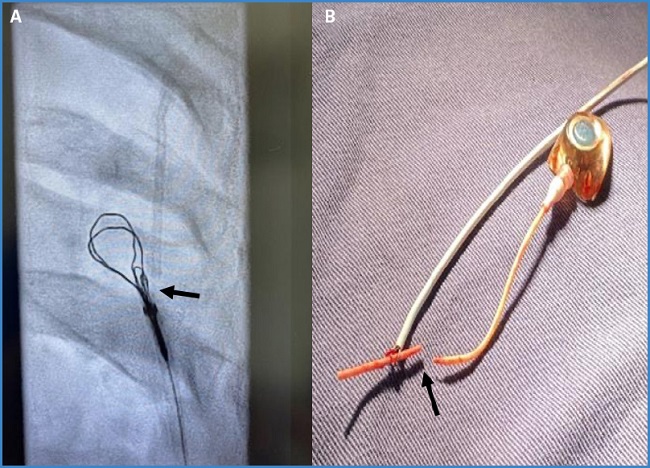

Se realiza heparinización de 80 UI por kg y se realiza punción de la vena femoral bajo guía ecográfica. Inicialmente se procede al paso de un introductor de 5 fr., de una guía hidrofilia y de un catéter multipropósito hasta la cava superior, canulando la vena yugular y la subclavia. Se cambia a un introductor de 6 fr. para el paso con catéter Snare® de lazo trilobulado (Standard Snare, EN2006020, 12-20 mm; Merit Medical Systems, South Jordan, Utah, EE. UU.). Se captura el segmento de catéter y se extrae (Fig. 2A).

Figura 2. A. Catéter Snare® de lazo trilobulado (flecha negra). Se visualiza la punta del catéter antes de la extracción. B. Después de la extracción se ve la fractura del catéter (flecha negra).